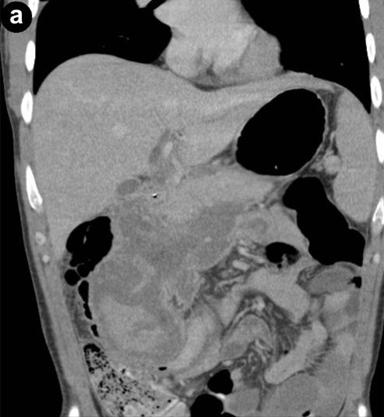

Duplex US and PVPCT are the most common first-line investigations in assessing acute pancreatitis. To enable detection of pseudoaneurysms, US examination must include pulsed or colour Doppler (duplex US) of all cystic masses to distinguish a pseudocyst from a pseudoaneurysm [20]. The sonographic appearance of a pseudoaneurysm changes when clot develops within its lumen rendering the diagnosis very difficult even with colour Doppler [21]. In the present series, US with colour Doppler failed to detect the presence of a pseudoaneurysm in two patients which were later diagnosed on PVPCT and arterial phase CT. Similar results have been observed in other studies, and most clinicians would conclude that the diagnostic value of Doppler US in the detection of pseudoaneurysms complicating pancreatitis is limited [22, 23]. Although PVPCT is a suitable non-invasive method for detecting pseudoaneurysms [22, 24, 25, 26], its role in the diagnosis of pseudoaneurysms is limited by its failure to identify smaller pseudoaneurysms [23, 27, 28]. In the present series, PVPCT failed to detect small pseudoaneurysms in five patients which were later diagnosed on arterial phase CT (Figure 3).

|

Figure 3. a. Portal venous phase contrast enhanced computed tomography (PVPCT) in a patient with a small pseudoaneurysm which is not demonstrated. b. Arterial phase computed tomography in the same patient demonstrates a small pseudoaneurysm (arrow). |

Arterial phase CT is a suitable first-line investigation for diagnosing pseudoaneurysms associated with pancreatitis with a similar sensitivity rate that of angiography [28, 29, 30]. In the present series, arterial phase CT detected all pseudoaneurysms when used as a first-line (n=2), second-line (n=4) and third-line investigation (n=1). Arterial phase CT has the additional benefit of planning further management by clearly demonstrating the arterial anatomy, providing a roadmap for further intervention. This allows for targeted visceral angiography as well as the identification of difficult cases prior to intervention. In this study, not all patients (n=3) underwent an arterial phase CT to confirm resolution of the pseudoaneurysm. One reason for this non-uniformity follow-up was due to the fact that two patients were embolised prior to 2007 when follow-up with arterial phase CT was not practiced routinely and one patient underwent a PVPCT to exclude an intra-abdominal collection where the pseudoaneurysm was shown to have resolved.